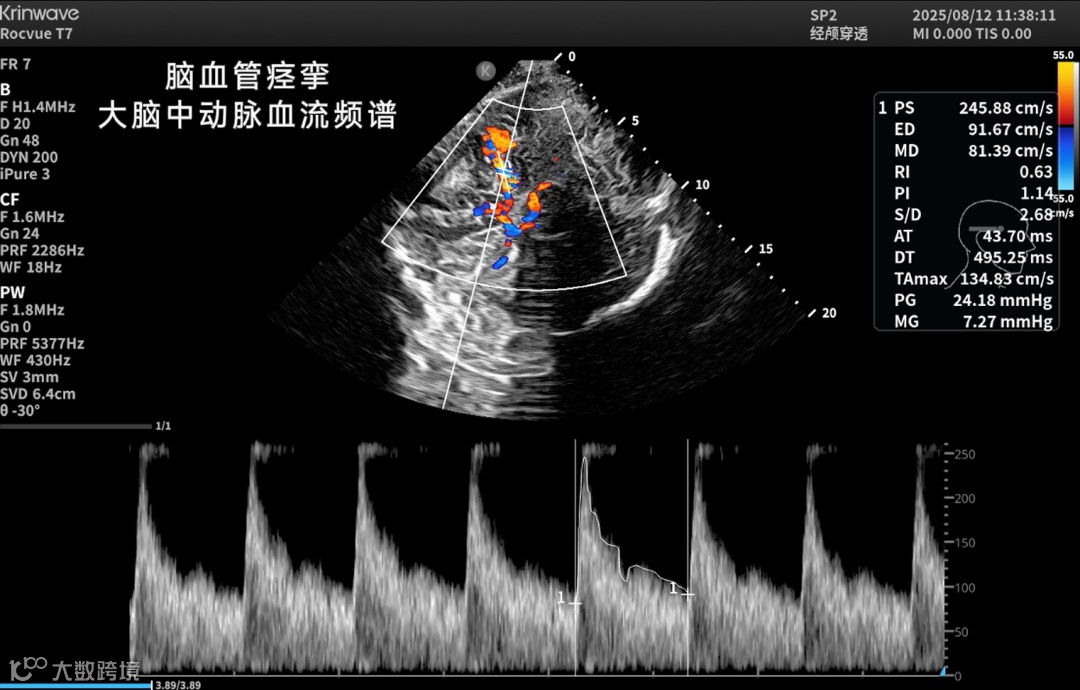

● 神经重症监测

床旁实时评估颅内压、脑血流动力、脑水肿及血肿变化;

● 脑卒中防治

实现院前识别、院中动态监测与干预评估;